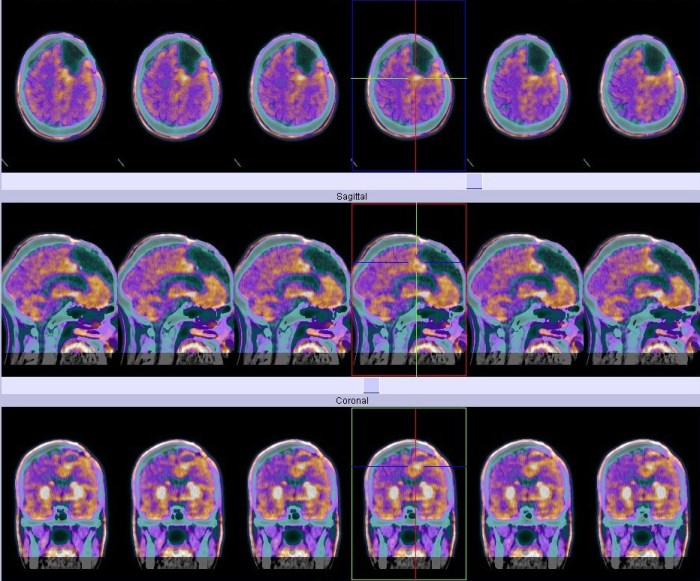

Quand Microwave News demanda un retour sur cette question à Philips, il nous envoya le graphique suivant :

Selon Philips, « Cela démontre clairement que l’augmentation des glioblastomes concerne juste deux régions du cerveau, les lobes temporal et frontal ». « Il n’y a aucune raison pour penser qu’un meilleur diagnostique favoriserait la présence de ces tumeurs à certains endroits par rapport à d’autres. Je ne suis pas en train dire que c’est forcément lié au téléphone portable, mais ça serait certainement la possibilité la plus logique. Après tout, les lobes temporal et frontal sont les parties les plus exposées aux radiations quand un téléphone est vissé à l’oreille. »

« Je ne pense à rien d’autre qui serait comptable de nos constations, » indiqua Philips, « Quoi d’autre se trouve à cet endroit ? »